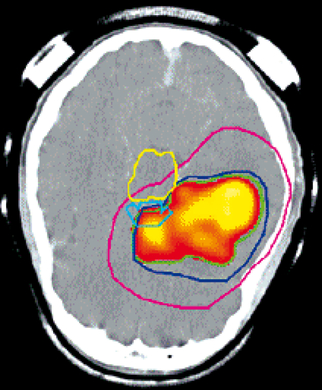

Schädel mit Isodosenlinien- bedeutende Vorteile für die Bestrahlung von Tumoren